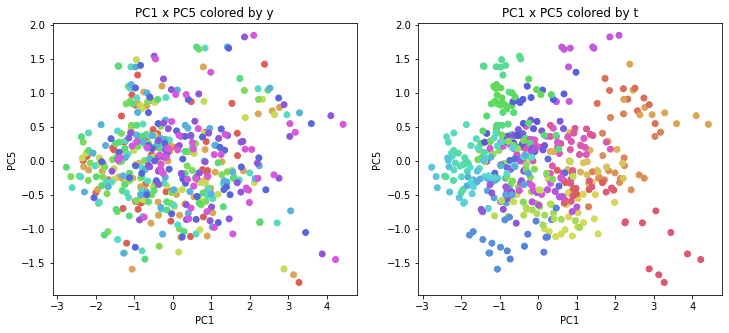

PCAの結果の第n主成分をPCnと表記します。

医療費データの場合と同様に、PCAの結果を見やすく表示するため、seabornのカラーパレットを使って、年月別、都道府県別に色分けして図示してみます(左側が年月別に色分け、右側が都道府県別に色分け)。PC1~PC8まで表示しました。

医療費データの場合ほどはっきりとはしていませんが、PC2が概ね時間の経過を表す成分で、残りの成分が時点によって変わらない地域の特徴を表す成分となっているようです。

また、PC1×PC3を見ると、47沖縄が他の都道府県からかなり離れたところに位置しており、沖縄の地域差が際立っているのが分かります。これは、以前別の記事で年齢階級のない健診データでPCAを実行した場合と似た結果となっています。

今回は、医療費データと同様に、健診データ240次元についてPCAを実行してみました。PCAの結果、医療費データの場合ほどはっきりしとはしていませんが、第2主成分が概ね時間の経過を表す成分で、時間軸に沿った全体的な動き(全国的な動き)を表しており、それ以外の成分が地域の特徴を表す成分で、この10年間あまり変わっていないことがわかりました。